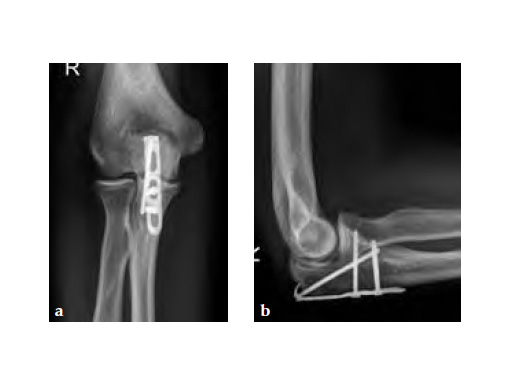

Fig 3ab X-rays 5 months postoperatively.